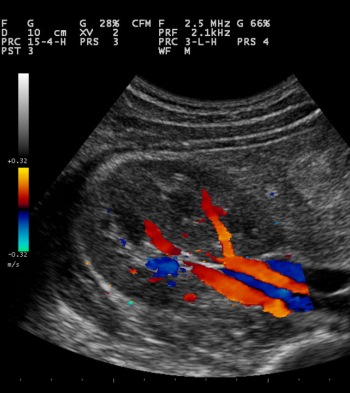

Color Doppler krvnih sudova vrata i glave je bezbolna, neinvazivna dijagnostička metoda kojom se može meriti protok krvi kroz krvne sudove vrata i glave. Ovom metodom se mogu otkriti suženja krvnih sudova, ili njihova proširenja (aneurizme). Na arterijama se mogu videti naslage ili plakovi koji sužavaju šupljinu krvnog suda.

Šta su kolor dopler karotida i transkranijelni dopler?

To su ultrazvučne metode koje omogućavaju neinvazivan prikaz protoka krvi kroz krvni sud i analizu stanja krvnog suda, što može uputiti na poremećaj protoka i prisustvo naslaga, odnosno suženje krvnog suda. Kritično sužen krvni sud onemogućava dotok krvi u mozak što može da dovede do moždanog udara. I kod manjih suženja, ponekad dodje do pojave moždanog udara, onda kad su naslage nestabilne pa se deo naslaga odvoji, koji nošen krvnom strujom može da zapuši manji krvni sud u glavi. Na pojavu naslaga utiču faktori koje ne možemo da promenimo kao godine ili nasleđe ali i oni koje mozemo a to su način ishrane, pušenje, regulacija povišenog šećera... Moguće je ispitivati stanje i protočnost velikih krvih sudova vrata (dopler karotida i vertebralnih arterija) koji snabdevaju mozak krvlju, a takođe i neposredno krvne sudove mozga (transkranijalni dopler- TCD). Obe ove metode su potpuno bezbolne i bezbedne.